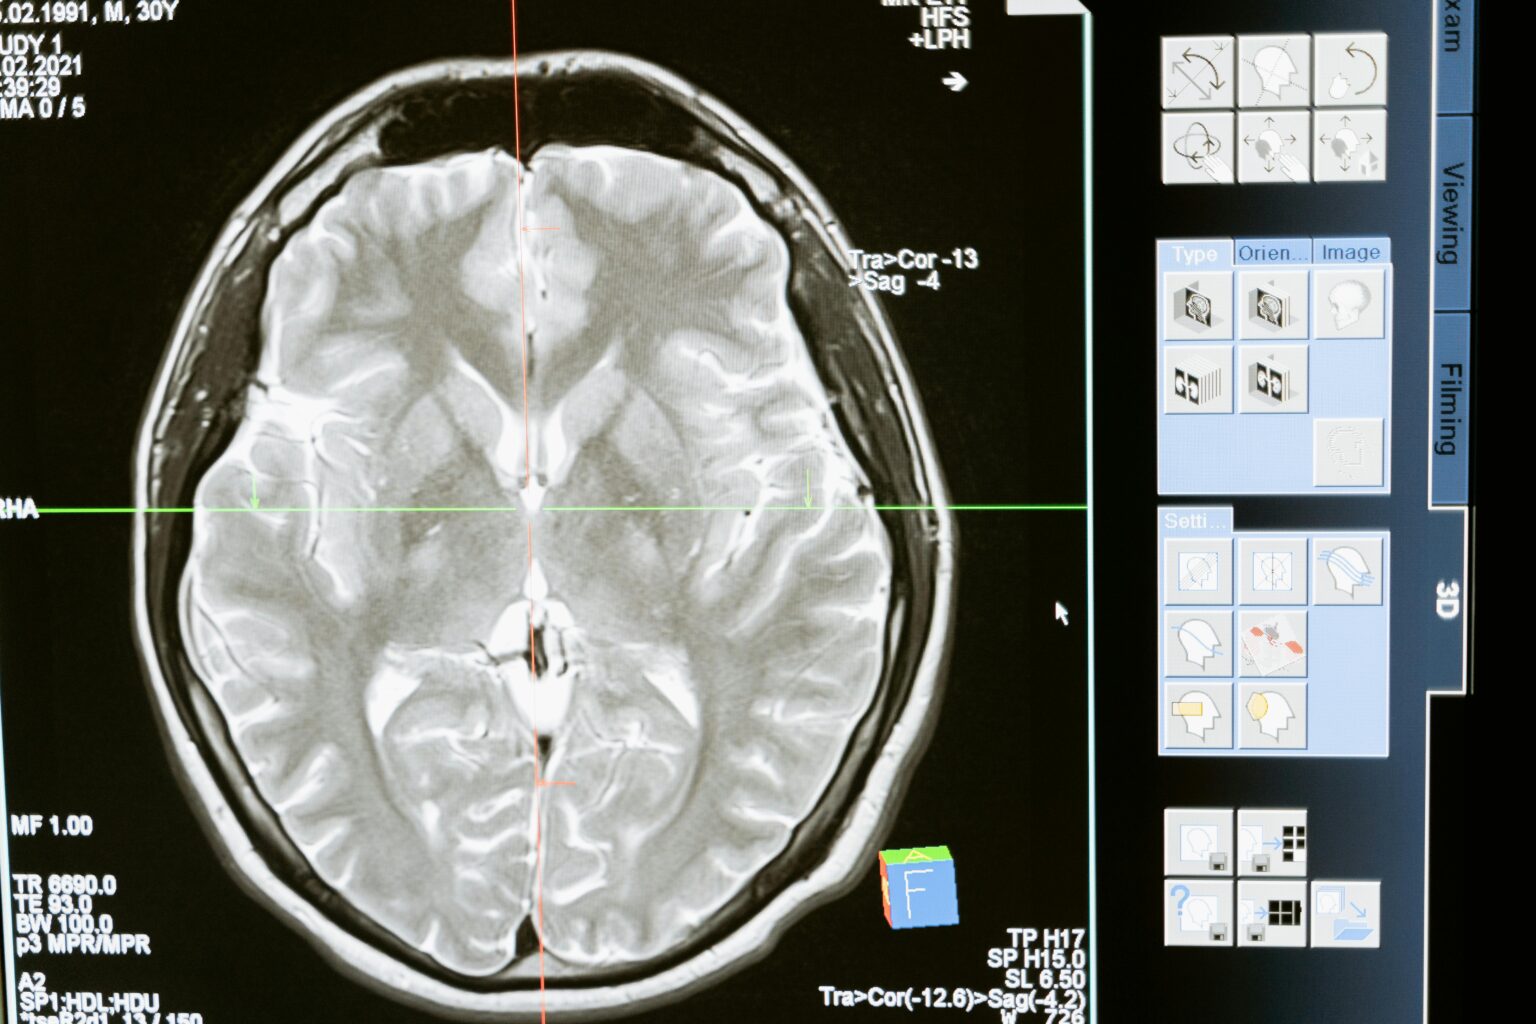

Specialists manage a wide spectrum of conditions, from mild concussions to severe traumatic brain injuries (TBI), which occur when an external force causes damage to the brain. Diagnostic tools are used to determine the extent of injury and guide treatment:

- Imaging studies (such as CT scans or MRIs)